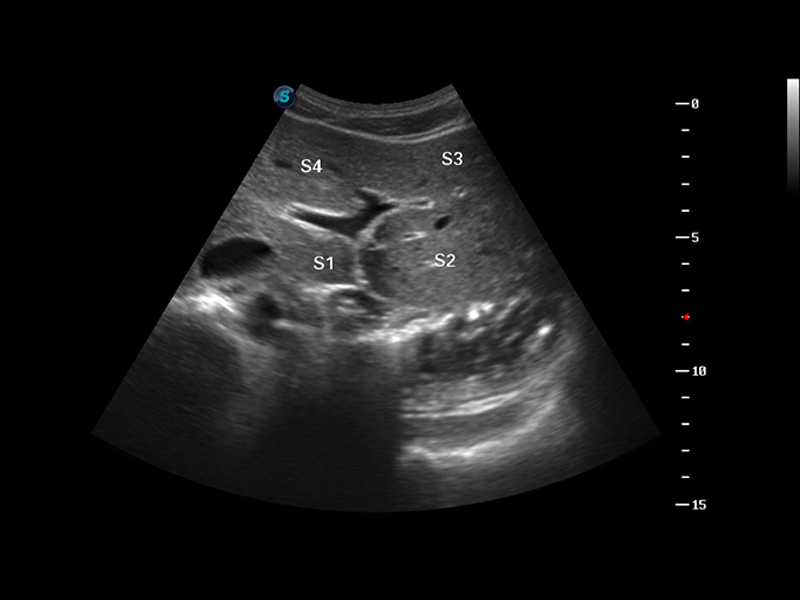

谐波成像